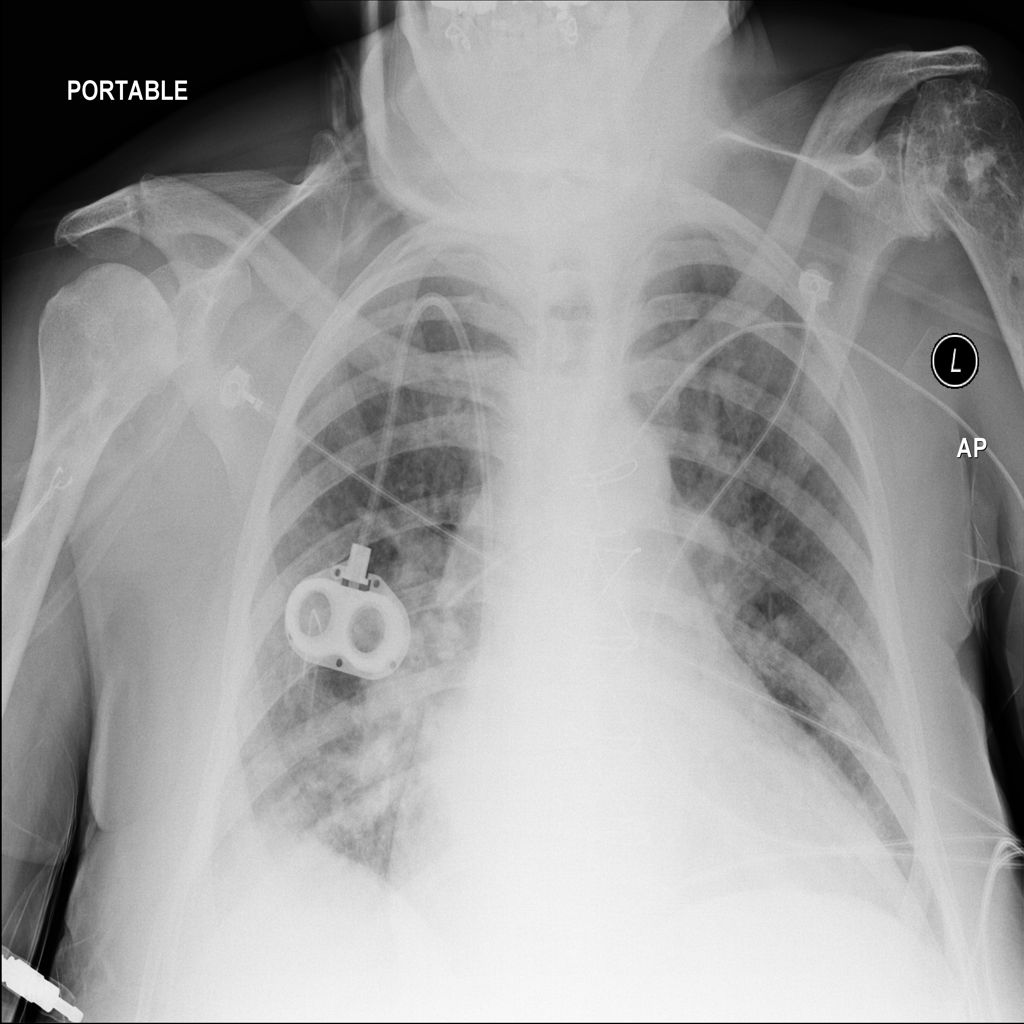

PAT-F3E7 · IMG-000Cardiomegaly

PAT-F3E7 · IMG-000

PA